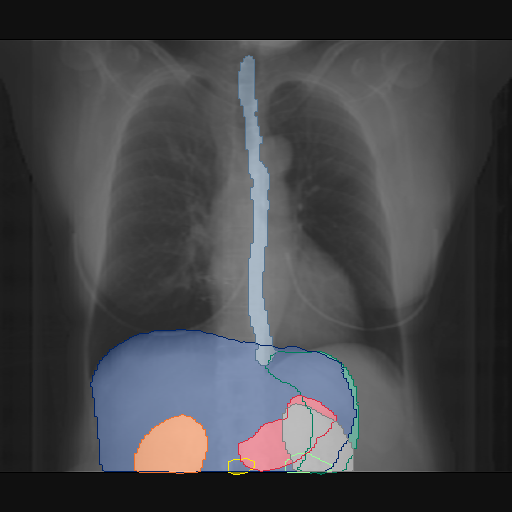

We show qualitative results for frontal projections in Fig. 2. We show a subset of classes belonging to the supercategories lungs, vascular systems, bones, and abdomen/digestive system. The predictions show minor deviations at the boundaries of the individual classes of the respiratory and vasculature system, while some inaccuracies become visible in the abdominal area. The qualitative results for the lateral projections are displayed in Fig. 2. Akin to the frontal view, the predictions show smoother borders but align with the ground truth. Apart from this, the segmentations provide matching insights on the thoracic anatomy with a slight deviation from the ground truth for both frontal and lateral views.

Fig. 2 shows quantitative segmentation results for frontal (top row) and lateral (bottom row) views. We display the class performances in the form of IoU (left), DICE (center), and Hausdorff distance (right) for each sample as a scatter plot with the mean performance for the classes shown by a line plot. Generally, we see performances for standard spinal classes, such as the thoracic vertebrae with average IoU-scores above 80%, while the average performance of rare vertebrae of the dataset belonging to the cervical and lumbar spine can drop down to 40%. In the frontal view, there exists more variance in thoracic vertebrae segmentation performance compared to the lateral view. Bone structures such as the sternum, clavicles, and scapula achieve IoUs in the mean from 85% to 95%. For ribs, we can see a noticeable performance drop for the anterior parts of the lower ribs independent of the side. The lower anterior ribs typically do not contain a large area, making them difficult to segment. This behavior is mirrored in the lateral view across the metrics. Abdominal classes can vary in segmentation quality as they occur in a nearly homogenous region. For example, while the liver or stomach are typically well-segmented, the duodenum and kidneys are more complex. Heart and Lung related classes show near-perfect segmentations with scores above 90% IoU. Breast tissue segmentation in comparison only achieves a mean of 70% mIoU. It can be noted that classes in the lateral view tend to have slightly better scores than their frontal counterparts.